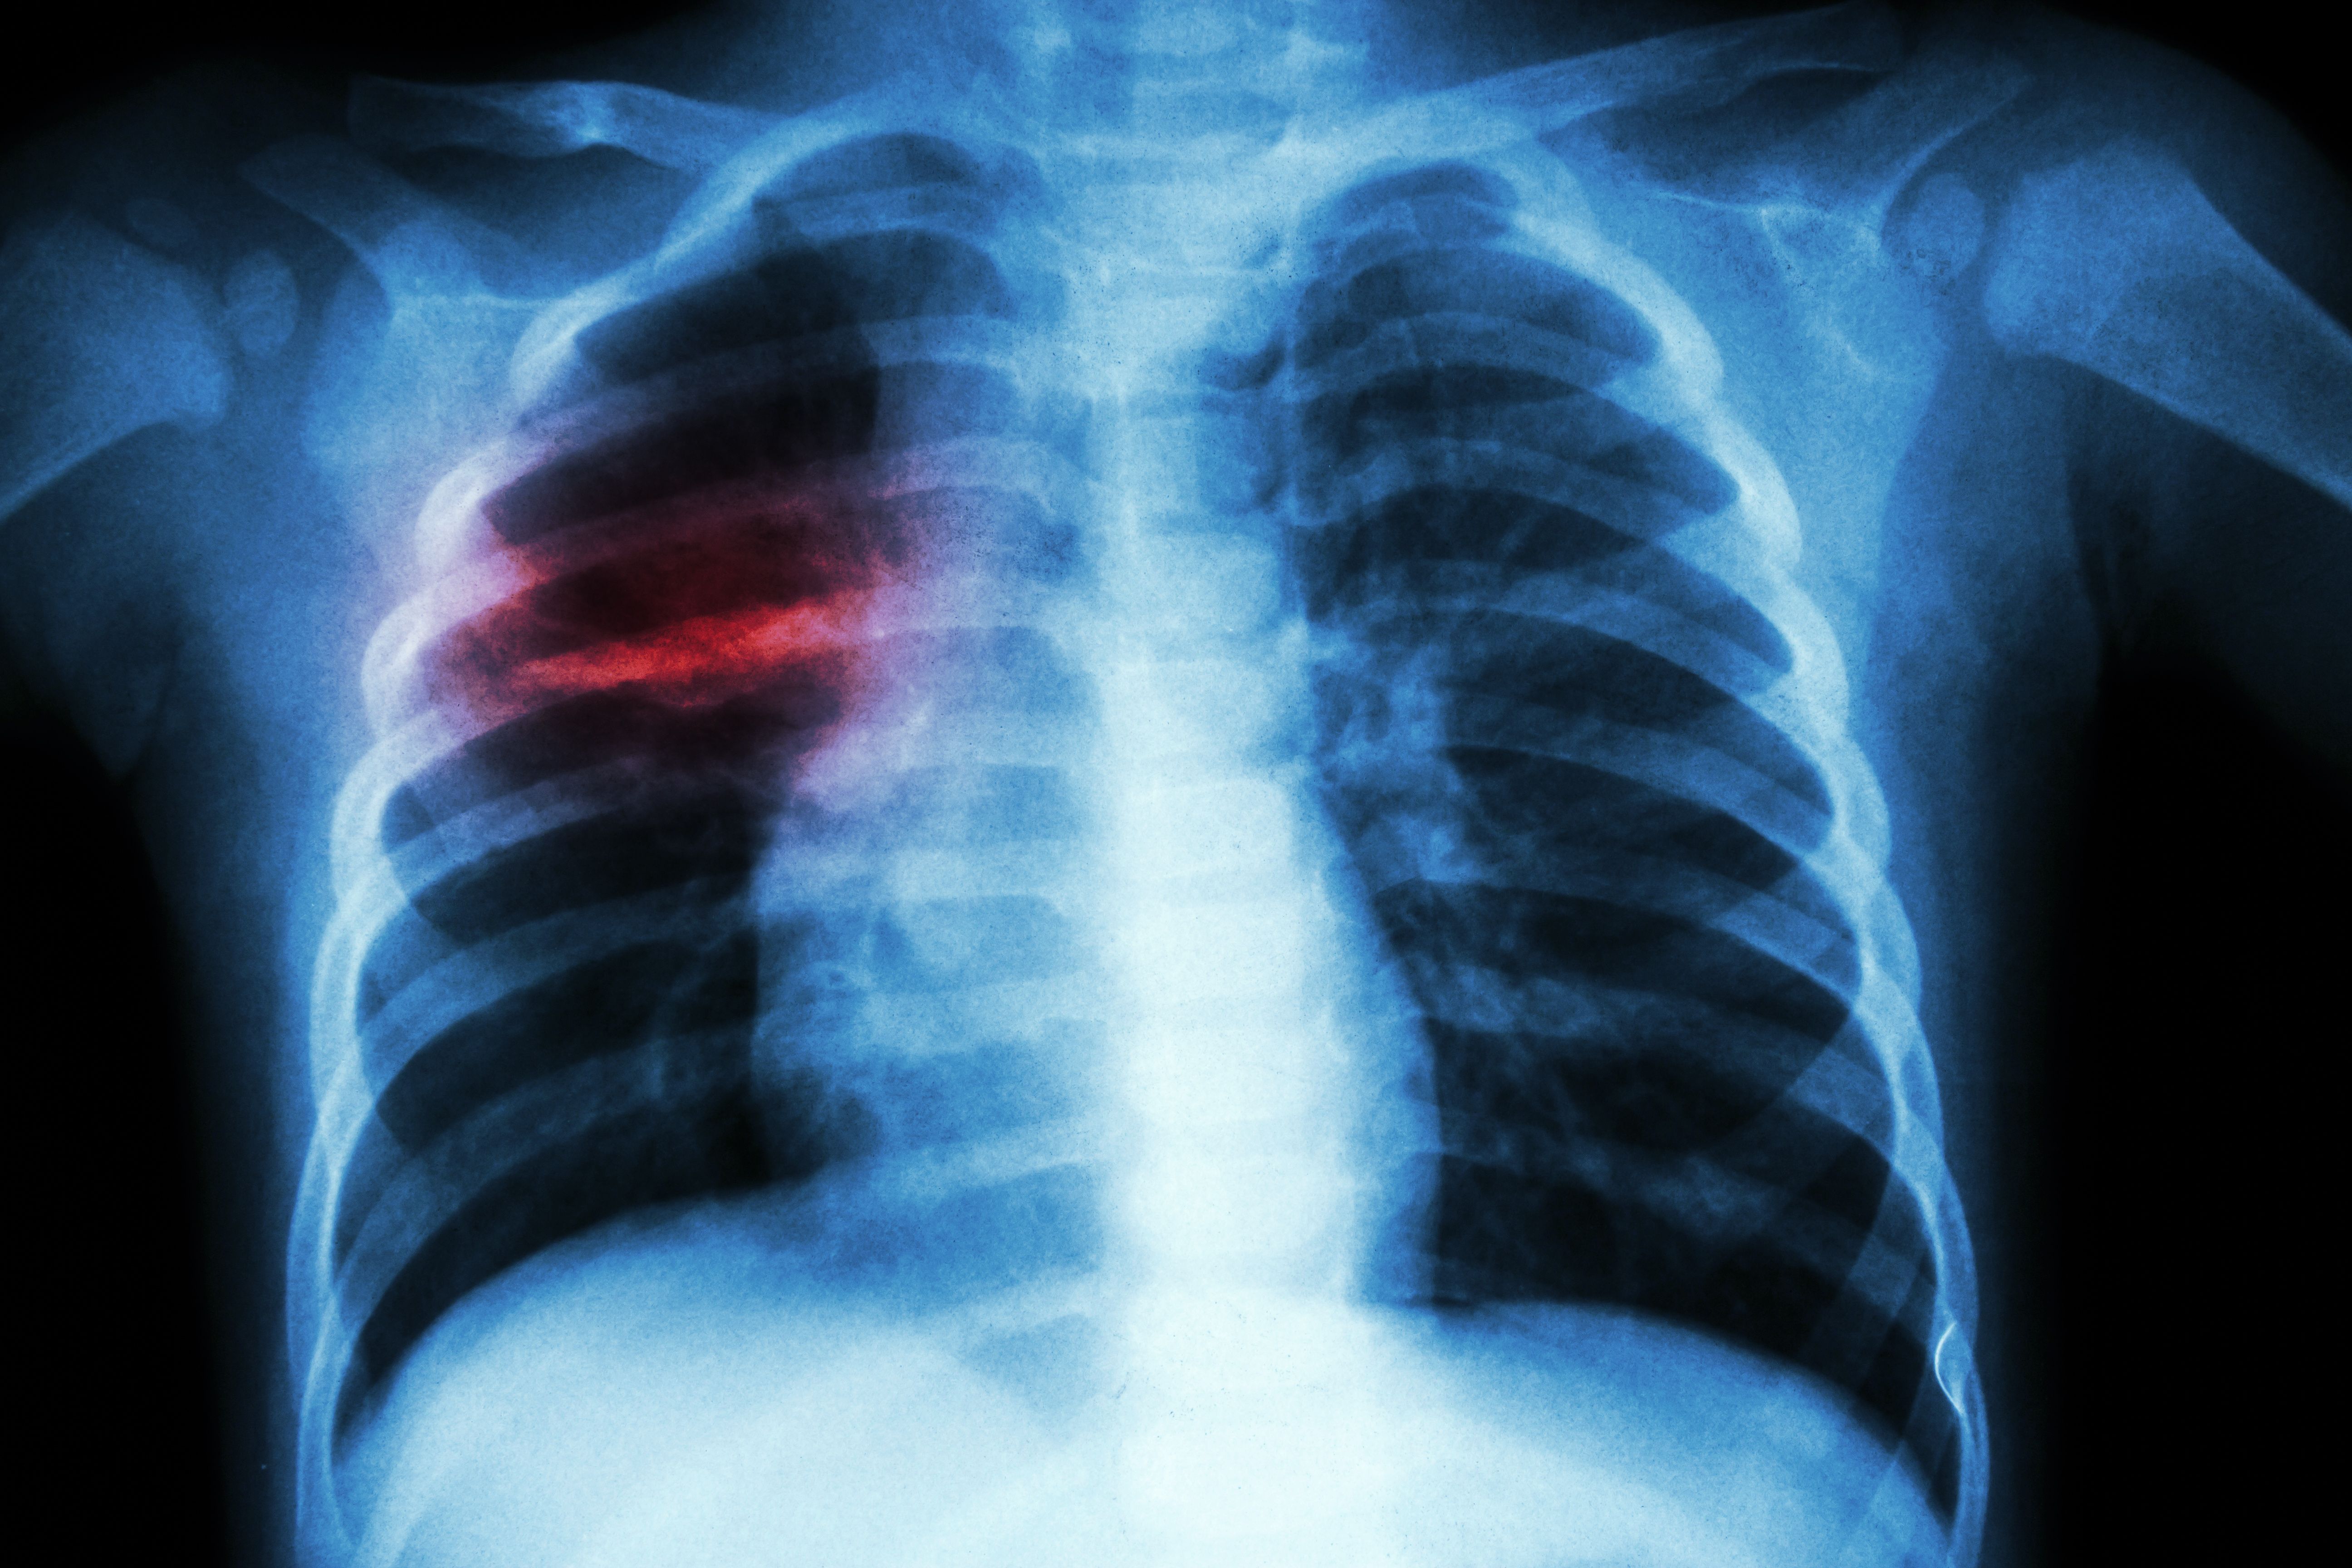

Procalcitonin to diagnose pneumonia in children with influenza-like illness | Image Credit: © stockdevil - © stockdevil - stock.adobe.com.

Investigators of a study published in Indian Pediatrics determined that procalcitonin (PCT) is an effective tool for point-of-care testing in patients with influenza-like illness (ILI) and fever longer than 4 days to guide indication for a chest radiograph (CXR) to rule out radiographic pneumonia.

Radiographic pneumonia was defined as, "Radiologist reporting definite or equivocal 'consolidation', 'infiltrate', and/or 'pneumonia' on the CXR. This definition was considered because patients with these radiological findings are usually treated with antibiotics for suspected bacterial etiology," stated the study authors.